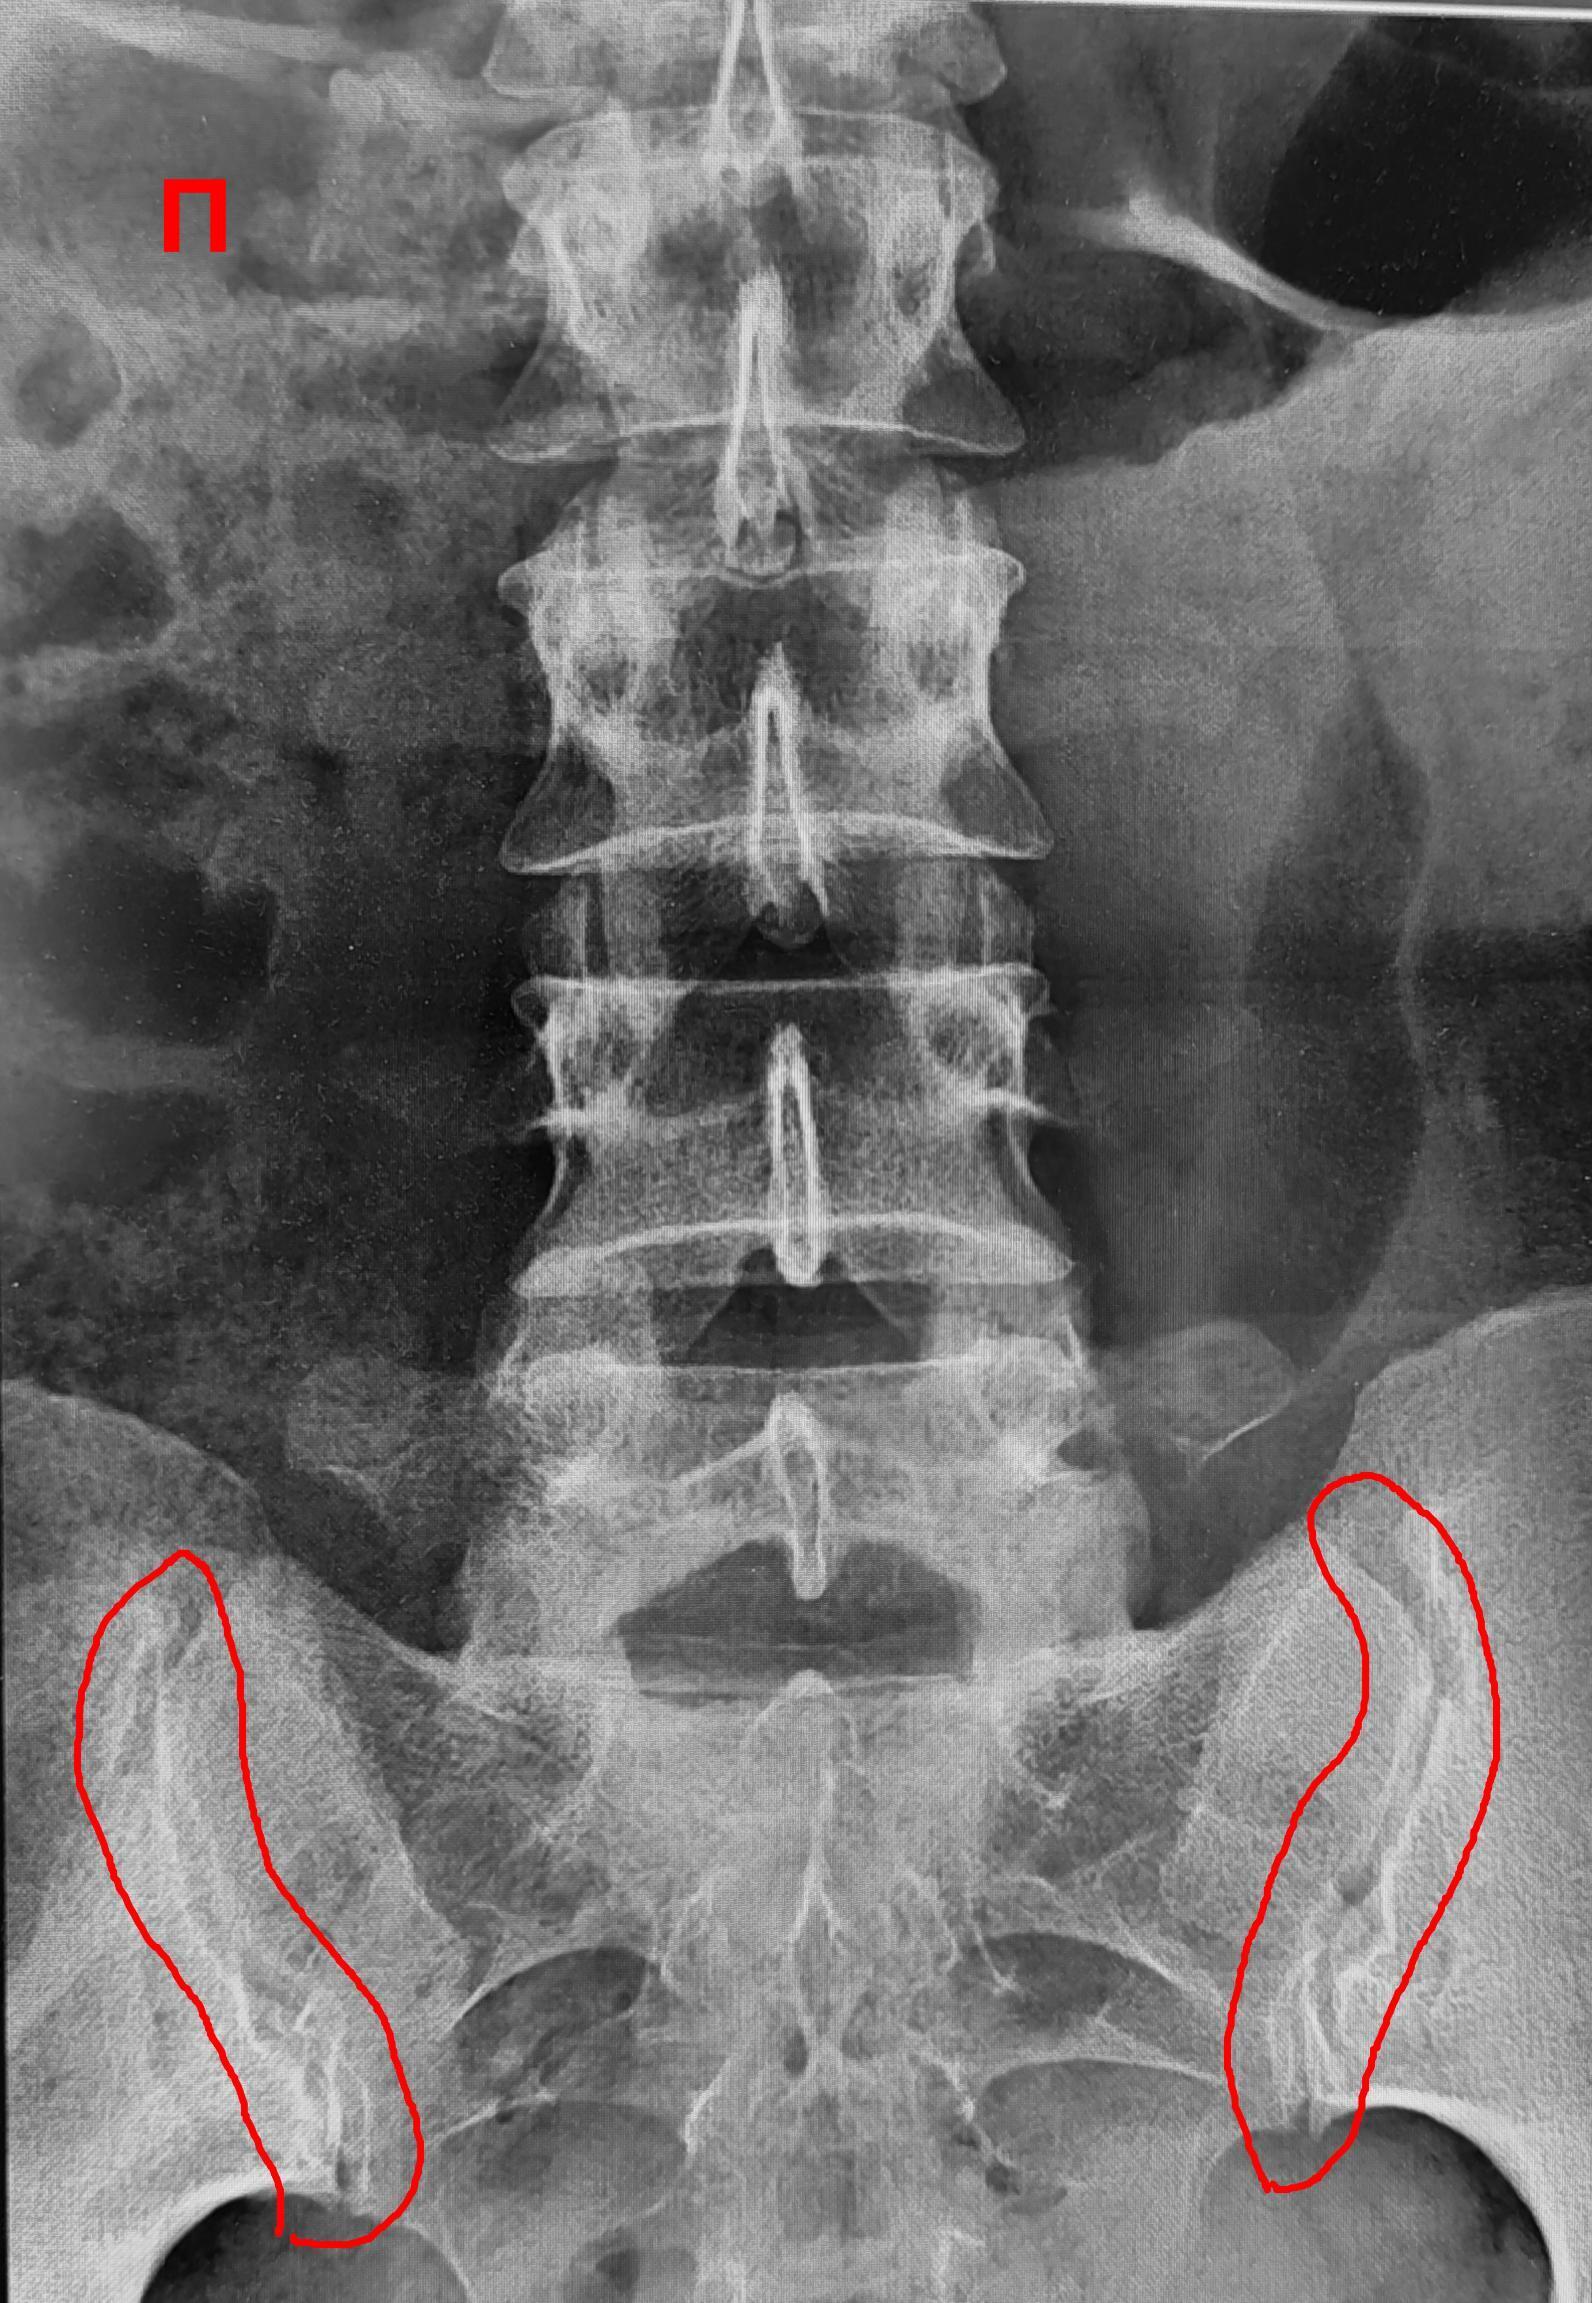

Рентгенограммы поясничного отдела позвоночника пациента с длительным, выраженным болевым синдромом(6 мес.) в пояснице, с временным эффектом от приема НПВС. При описании снимков выраженной костной патологии в поясничном отделе позвоночника не выявлено: структура тел позвонков не изменена, травматических, деструктивных изменений не выявлено, субхондральный склероз замыкательных пластин тел позвонков отсутствует, краевые остеофиты тел позвонков не выявлены, имеется не выраженное неравномерное сужение межпозвонковых щелей как начальное проявления остеохондроза-такая рентгенологическая картина не дает столь выраженного и длительного болевого синдрома.

Обращают на себя внимание крестцово-подвздошные сочленения(КПС),отмечается неравномерное не выраженное сужение щелей КПС с локальными участками расширения, субхондральный склероз- более выраженный слева, имеются двусторонние краевые остеофиты, в нижней трети левого КПС суставная щель не ровная, "изъеденная", по причине наличия единичных эрозий костной ткани. Заключение: Двусторонний сакроилиит 2 ст.(более выраженный слева).

В дальнейшем пациенту потребуется стац. обследование в ревматологическом отделении т.к. наиболее часто сакроилиит является проявлением анкилозирующего спондилита(болезнь Бехтерева), потребуются такие обследования: